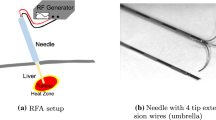

Needle-based intervention is part of minimally invasive surgery and has the benefit of allowing the reach of deep internal organ structures while limiting trauma. However, reaching good performance requires a skilled practitioner. This paper presents a needle-insertion training simulator for the liver based on the finite element method. One of the main challenges in developing realistic training simulators is to use fine meshes to represent organ deformations accurately while keeping a real-time constraint in the speed of computation to allow interactivity of the simulator. This is especially true for simulating accurately the region of the organs where the needle is inserted. In this paper, we propose the use of model order reduction to allow drastic gains in performance. To simulate accurately the liver which undergoes highly nonlinear local deformation along the needle-insertion path, we propose a new partition method for model order reduction: applied to the liver, we can perform FEM computations on a high-resolution mesh on the part in interaction with the needle while having model reduction elsewhere for greater computational performances. We show the combined methods with an interactive simulation of percutaneous needle-based interventions for tumor biopsy/ablation using patient-based anatomy.